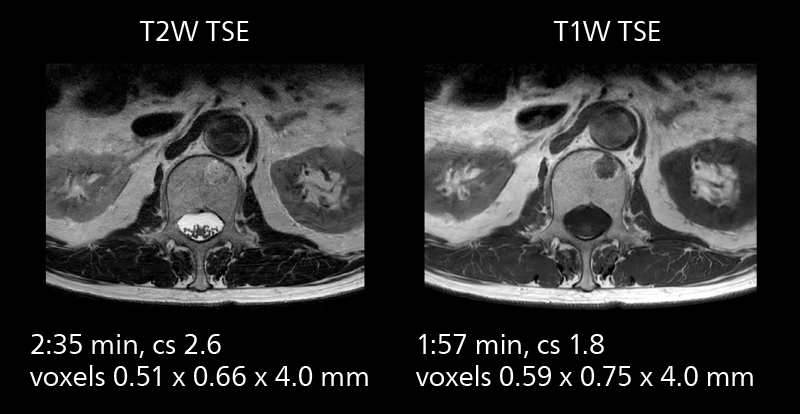

Lumbar spine MRI

Crisp images are obtained with high resolution and short scan times using Elition X. A cyst can be seen.